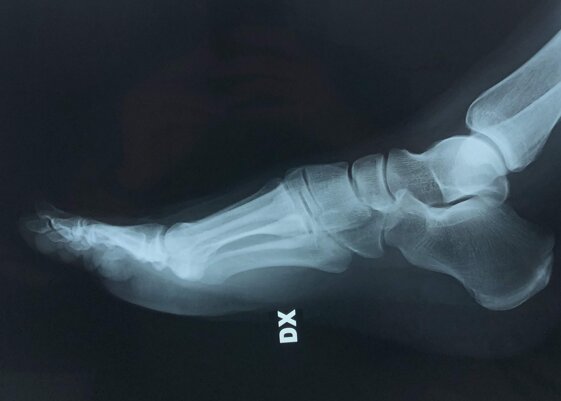

In alto a sinistra foto pre-operatoria piede destro in pz con Alluce Valgo.

In alto a destra ed in basso a sinistra radiografie pre-operatorie dei piedi sotto carico in AP e LL. La pz è stata operata con accesso mini-invasivo, per l’osteotomia del I MT non sono stati utilizzati mezzi di sintesi metallici ma un pin riassorbibile; nel caso specifico non ho effettuato l’osteotomia di F1 I dito in quanto la qualità dell’osso non era ottimale